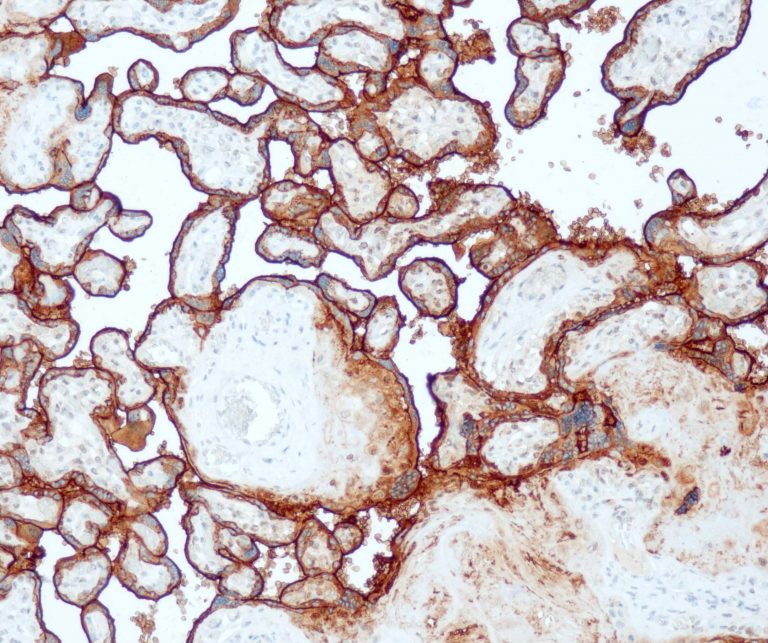

Lung Pathology